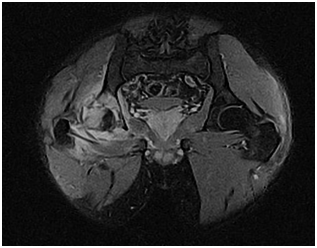

Subperiosteal abscess might be present, MRI tends to overestimate the extent of infection due to difficulty distinguishing adjacent reactive edema from frank marrow infection (Figure 11).

Figure 11 MRI of the legs T2WI showing large subperiosteal abscess extending along the tibia. The marrow signal abnormality in the proximal tibial epiphysis, metaphysis and diaphysis is consistent with osteomyelitis. There is soft tissue cellulitis and myositis.